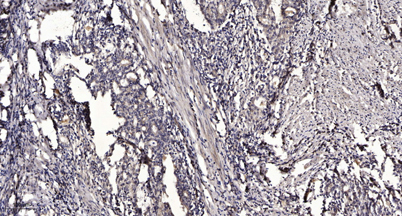

Shb (phospho Tyr246) rabbit pAb

Product name: Shb (phospho Tyr246) rabbit pAb

Dilutions: WB 1:500-2000;IHC-p 1:50-300